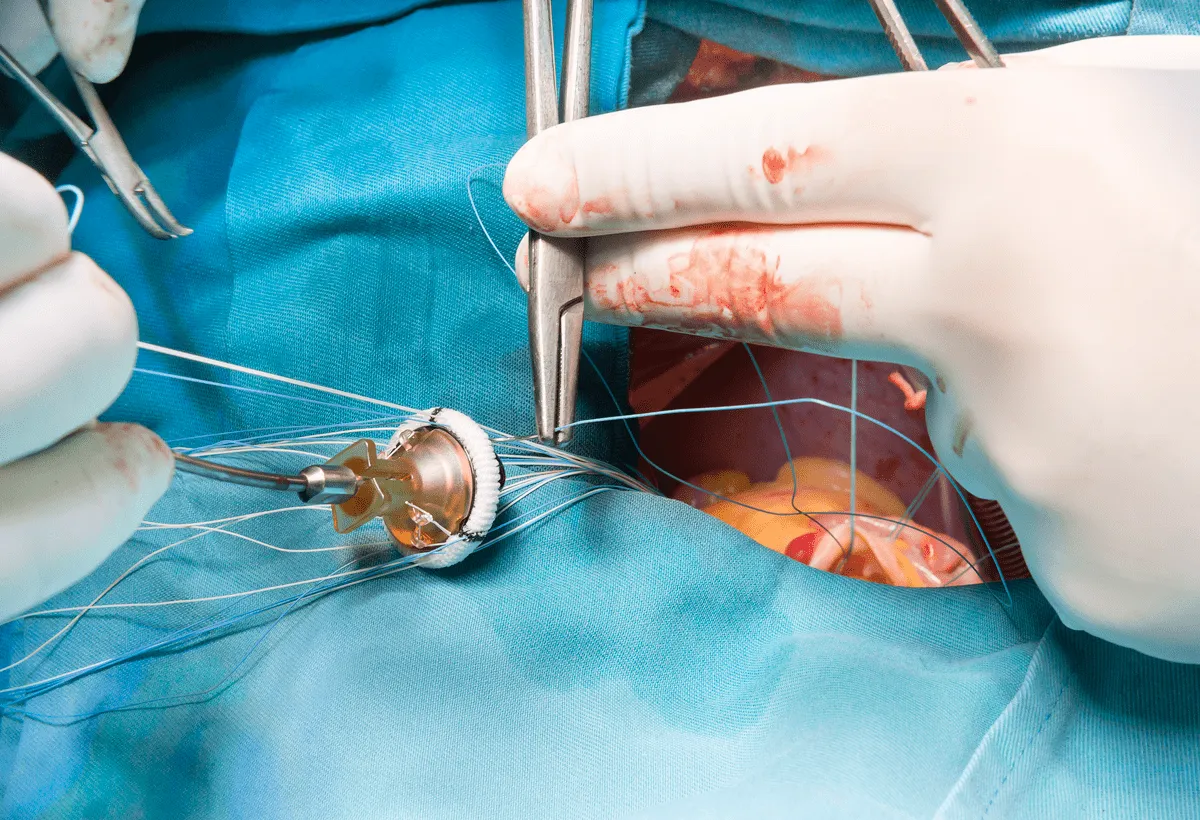

Progressão da estenose aórtica e DRC

Progressão da estenose aórtica e DRCCada vez entendemos mais o impacto da DRC em desfechos cardiovasculares. O nefrologista deve agir não apenas prevenindo a progressão da DRC, mas investigando as inúmeras complicações. Confere esse artigo sobre a relação entre DRC e estenose aórtica

Valkercyo Feitosa

3 anos atrás